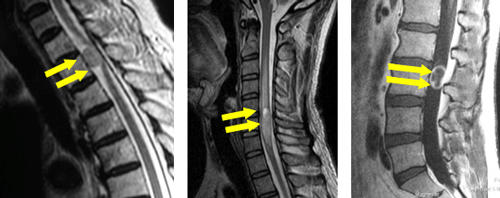

脊髄腫瘍摘出術

対象となる疾患は、脊髄や神経もしくは周囲にできた腫瘍、あるいは血管奇形などです。大きさや腫瘍の種類にもよりますが、基本的に放置すると増大して脊髄の圧迫は進行するので摘出術を考慮します。直接神経組織を触る手術になりますので、術後は多かれ少なかれ神経のダメージによる手足の麻痺が出ますが、当院では神経のダメージを最小限に抑えるため、最新の顕微鏡や特殊なモニタリング装置を用いて手術を行っています。

-

左から脊髄髄外腫瘍、脊髄髄内腫瘍、馬尾腫瘍のMRI画像です。